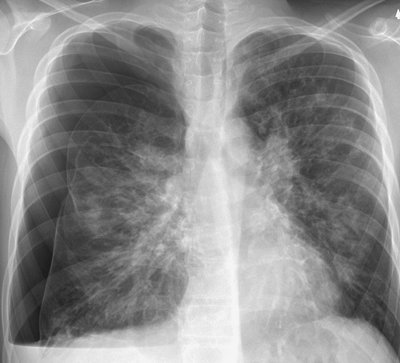

FIGURE 9-12. Re-expansion pulmonary edema. A: PA chest radiograph of a 78-year-old woman with metastatic breast cancer shows a large left pleural effusion associated with collapse of the left lung and shift of the mediastinum to the right. These findings suggest tension hydrothorax. B: PA chest radiograph after placement of a left chest tube and adequate drainage of pleural fluid shows re-expansion pulmonary edema on the left.